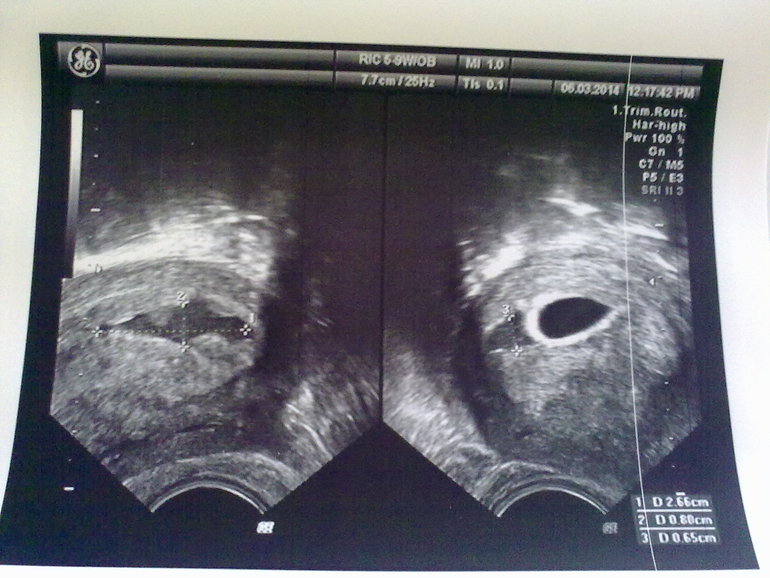

Вчера такой пост создавала, но видимо я его случайно удалила. Так вот мое первое узи: мешочек и эмбриончик я вижу отчетливо..... А вот смущает , рядом тоже мешочек или что это? Я в интернете нашла похожее , типа двойня на 5 неделе. Узистка вообще ничего не сказала, кроме как все хорошо , только матка чуть в тонусе. Девочки, ваши предположения? Фото под кат

А) это может быть отслоение, но никаких выделений и болей нет

Б) еще предположение, что так выглядит тонус